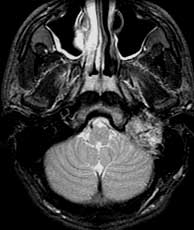

T2 SE axials

Findings: Mostly bright signal mass in the left medial skull base which abuts the basiocciput (basi) and invades the left external auditory canal (eac). The mass has several linear and curvilinear foci of decreased signal within.